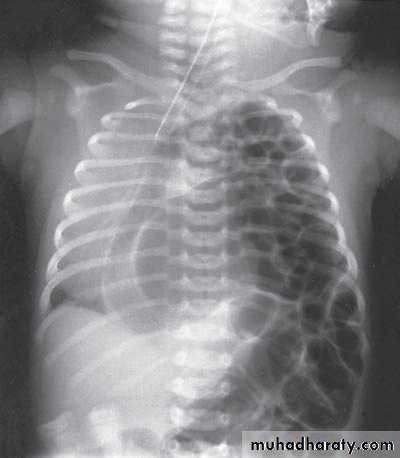

Bowel Obstruction

Tutorial